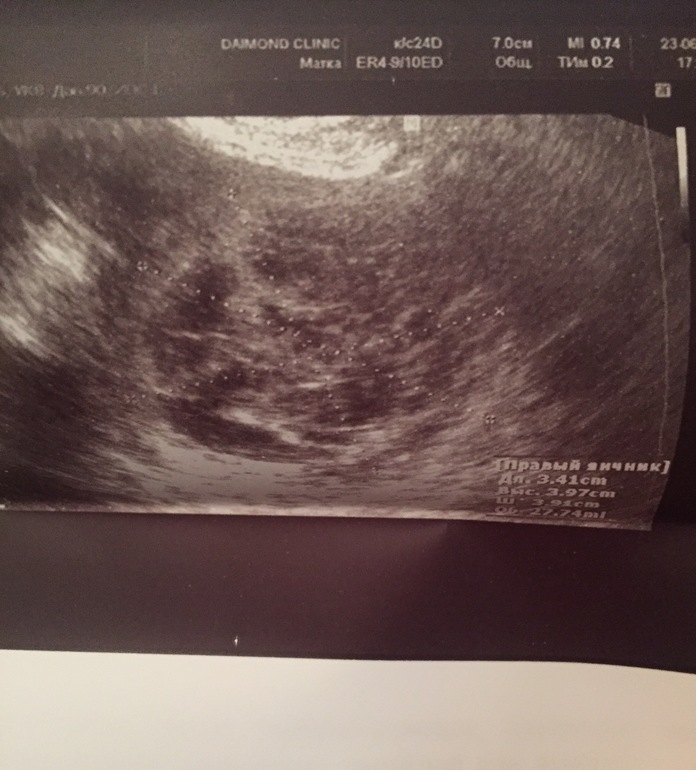

Потом в 17:30 пошла на фолликулометрию и обнаружили что овуляция была, но неизвестно когда (позавчера или сегодня неизвестно) и что в пя кровооизлияние😓 Это опасно? Сказали особо не надеятся т к неизвестно что за фолликул и т д, может спермики не дошли вообще или погибли?

Вот фото узи